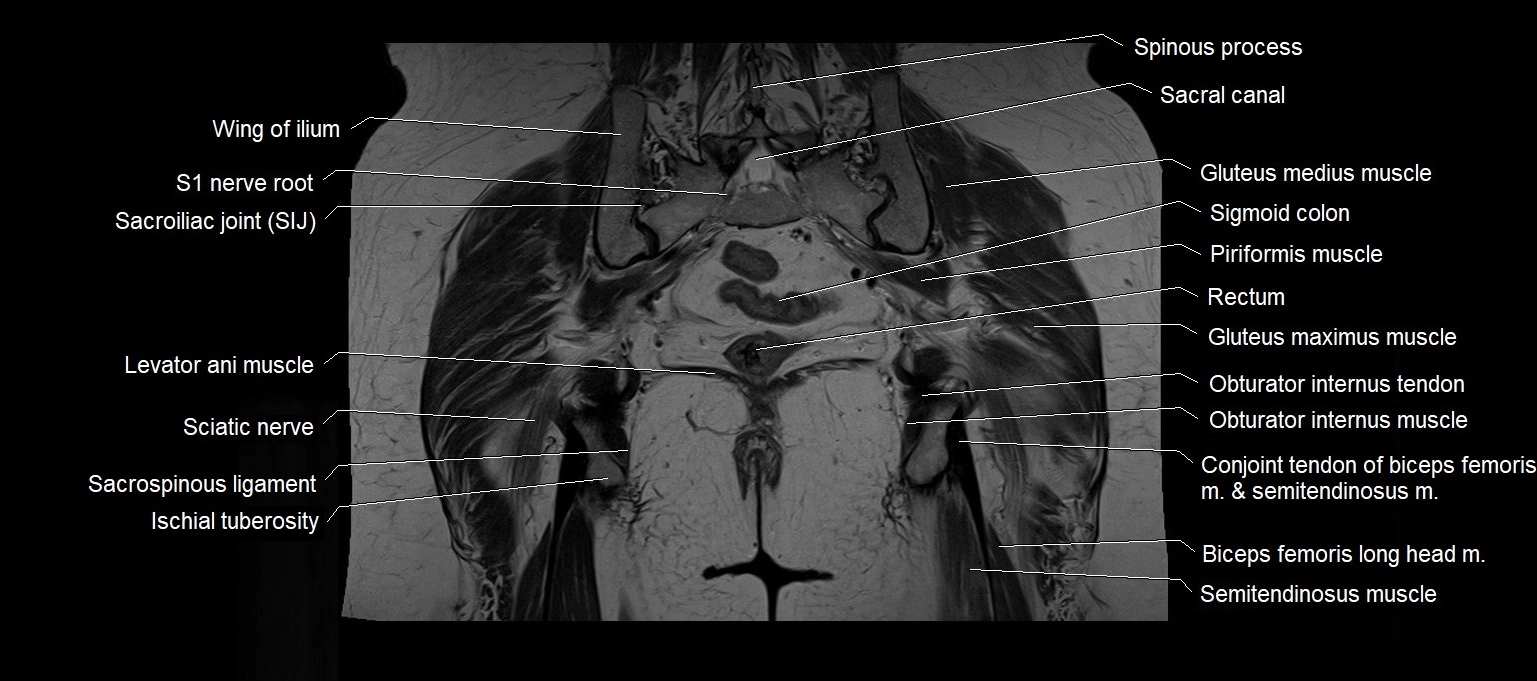

MRI images